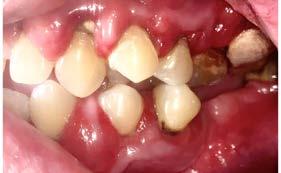

Figura 3. Fotografías intraorales.

hace 8 años por lo que toma 30 mg de nifedipino cada 12 horas, amlodipino 5 mg cada 24 horas, telmisartan 40 mg cada 12 horas y metropolol 100 mg cada 12 horas, además comenta padecer diabetes mellitus tipo II desde hace 7 años por lo que también toma 50 mg de metformina cada 12 horas y dapagliflozina 10 mg cada 24 horas. Clínicamente se observó una encía roja y sangrante, profundos sondeos, una notable hiperplasia gingival, depósitos de cálculo y movilidad dental grado III en todos los órganos dentarios a excepción del segundo premolar superior derecho al canino superior izquierdo, quienes presentaban una movilidad grado II. Radiográficamente se encontró una pérdida de inserción radiográfica avanzada generalizada

en la arcada inferior, y grupos molares de ambos cuadrantes superiores (Figura 1), los únicos órganos dentarios con posibilidad de preservación en boca a través de terapia periodontal se encontraron en el sector anterior de la arcada superior anteriormente mencionados con movilidad grado II

(Figura 2). Por lo que se diagnostica con periodontitis generalizada, estado IV, grado C (Figura 3).